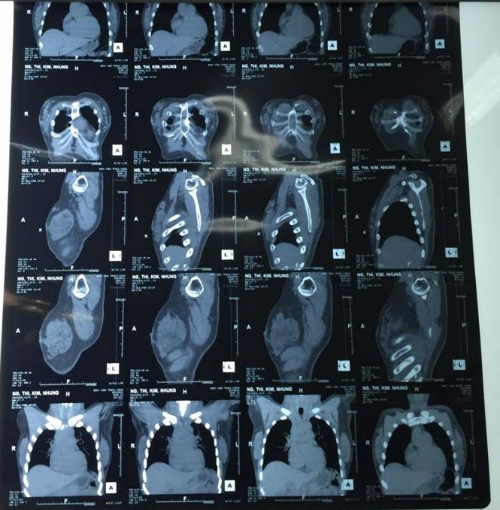

Khi tới BV Trưng Vương thăm khám, các bác sĩ ghi nhận khối cứng chắc ở hai má. Vùng ngực có nhiều khối u chắc, kích thước đa dạng và rải rác khắp tuyến vú hai bên. CT Scan cho thấy nhiều nốt cản quang nằm rải rác ở mô mỡ và mô tuyến vú.

Kết quả CT Scan của bà Hoa. Ảnh: vnexpress.net.

Bác sĩ Phạm Trịnh Quốc Khanh, Trưởng Khoa Phỏng Tạo hình Thẩm mỹ Bệnh viện Trưng Vương cho biết, bệnh nhân đã được phẫu thuật cắt trọn mô tuyến vú hai bên.

Kết quả giải phẫu ghi nhận mô mỡ, mô tuyến vú hai bên của bà Hoa có nhiều u silicon, nặng khoảng 500g. Ngoài ra có vài u nhỏ kích thước khoảng 5 mm cứng chắc, màu đen xám hai bên vú.